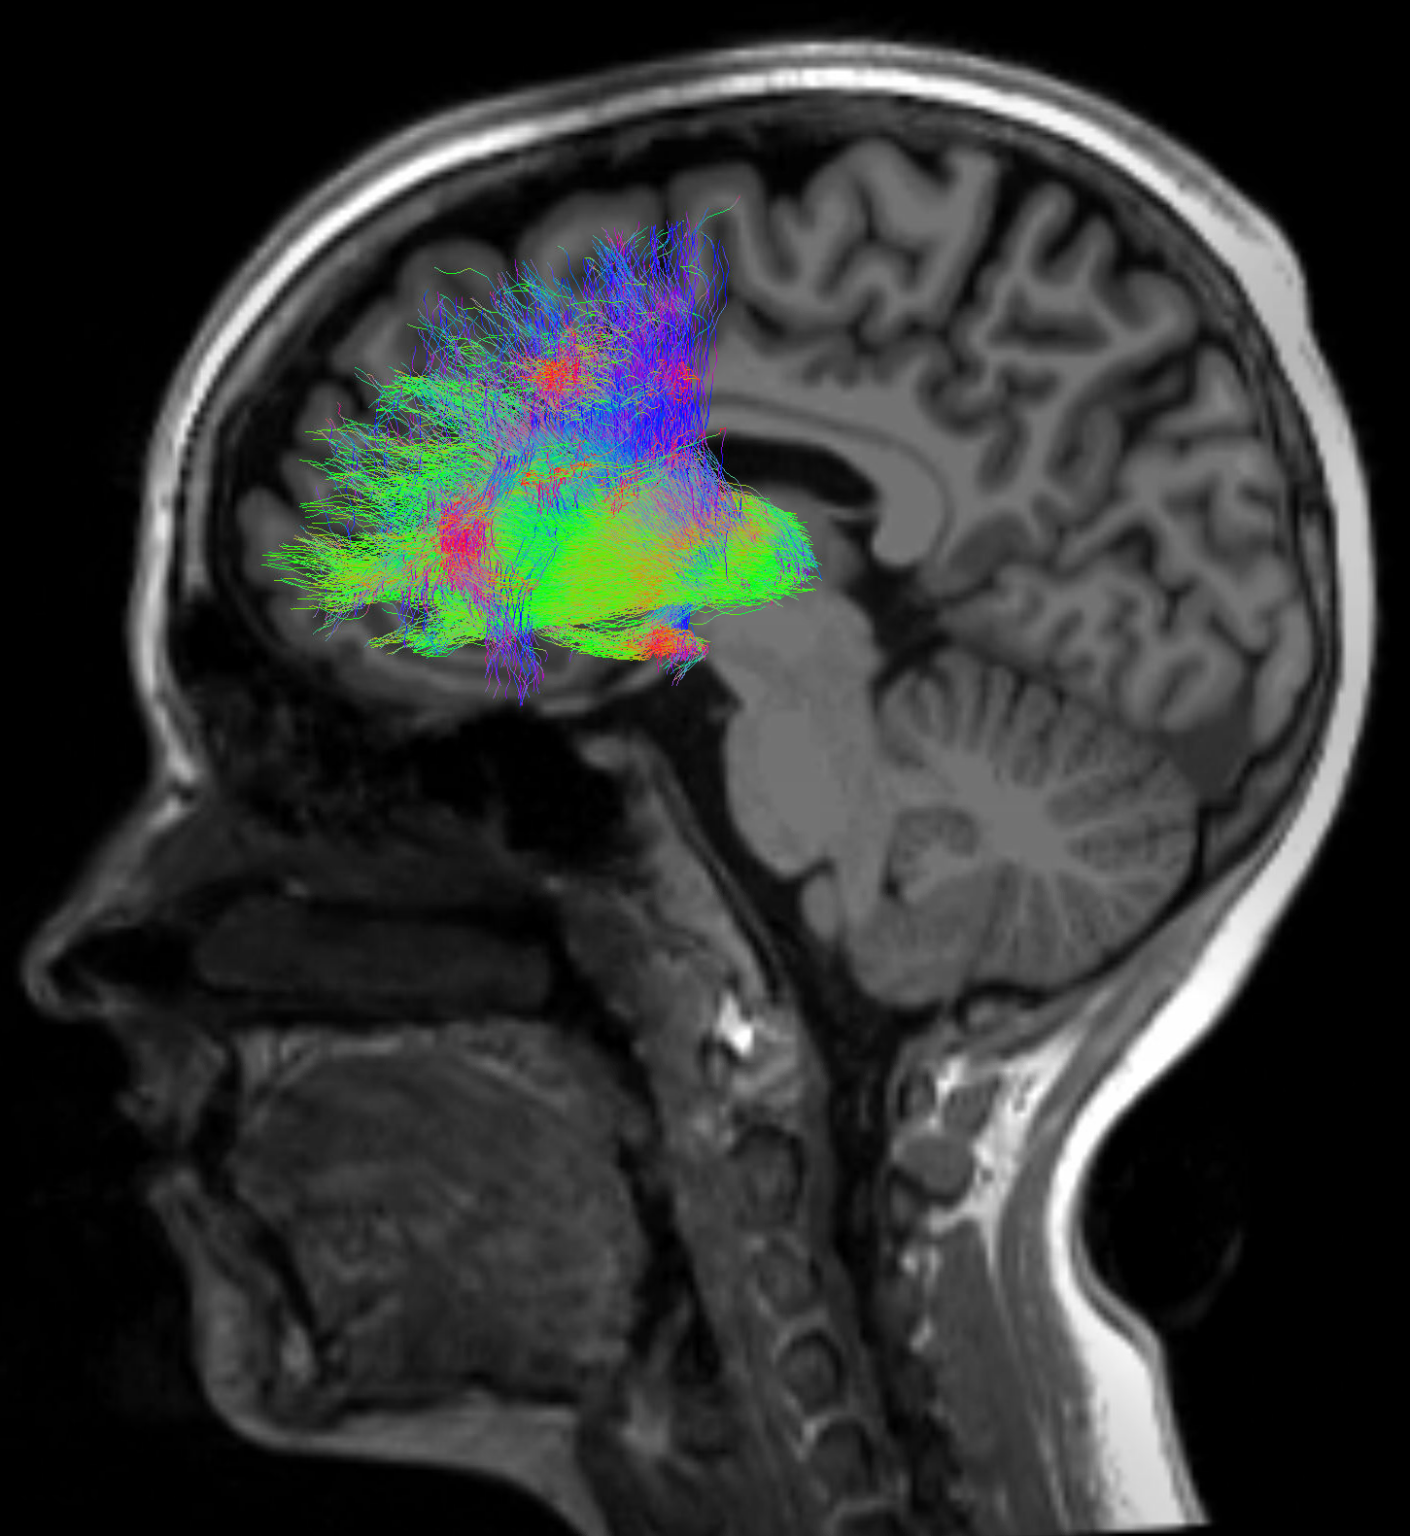

Groundbreaking study links cognition and brain networks before the first psychotic break

Early detection opens the door to intervention via noninvasive neuromodulation for those with treatment-resistant symptoms of psychotic disorders like schizophrenia. -